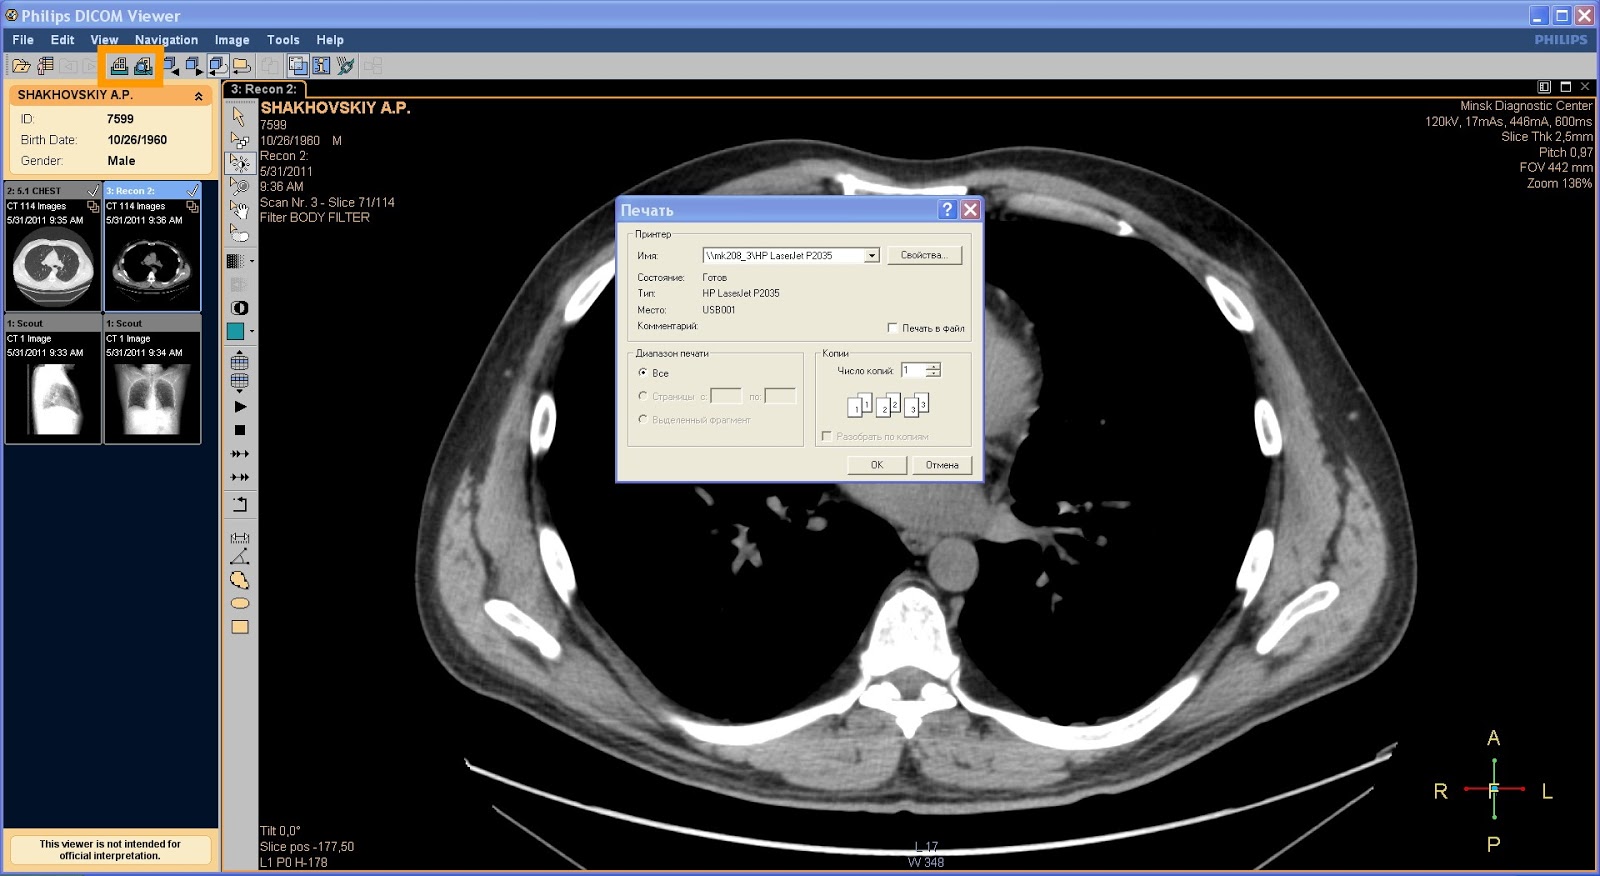

Лазерная камера сетевая для печати изображений на пленке стандарт dicom